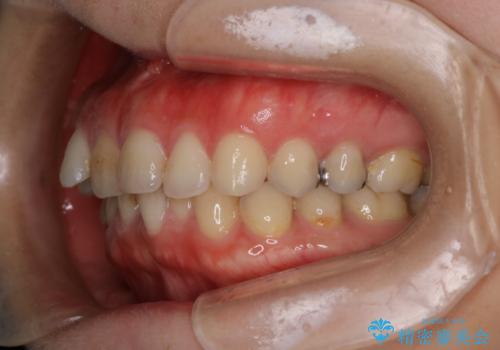

【下顎前歯の抜歯矯正】マウスピース矯正

- 下顎前歯の叢生を主訴に来院されました。

臼歯関係の状態から下顎前歯一本の抜歯を行う治療計画を立て、インビザラインを使用して治療を行いました。

今回の抜歯ケースはインビザラインでも綺麗に治ります。